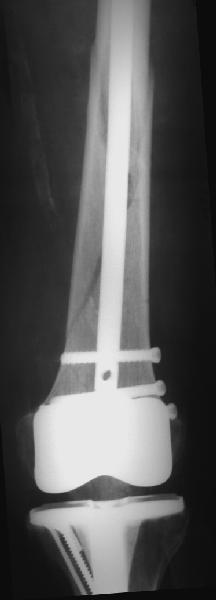

Хотя закрытый остеосинтез блокированным гвоздем выглядит технически проще, особенно при диафизарных переломах. Не говоря о биомеханических преимуществах внутрикостного имплантата, еще меньшей инвазивности, возможности динамизации при проблемах со сращением... Стоимость гвоздей и пластин сопоставимая, на рынке есть масса отечественных предложений.

В приложении - недавний перипротезный перелом.